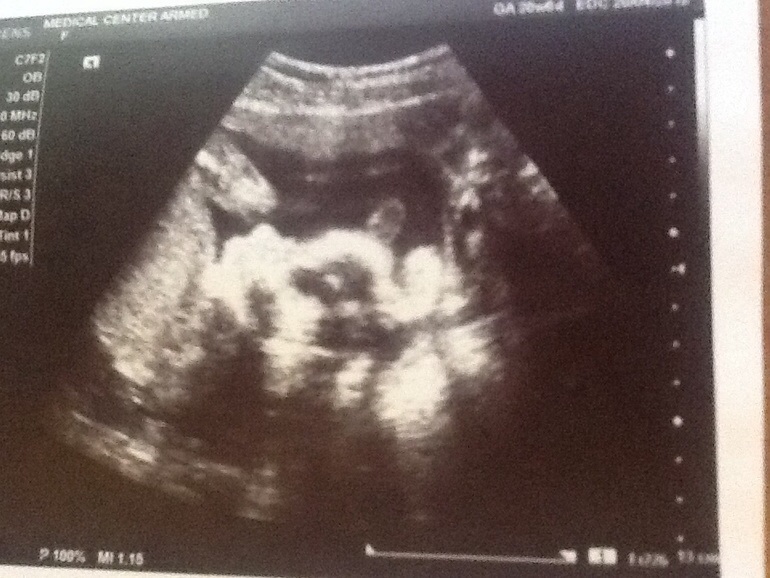

Ошибиться на таком сроке трудно! Судите сами, это фото моего сыночка в 16 недель. Смотреть в центр кадра и видеть то, что видится))) с дочей такого фото нет, но врачу верю, что там что-то другое))))